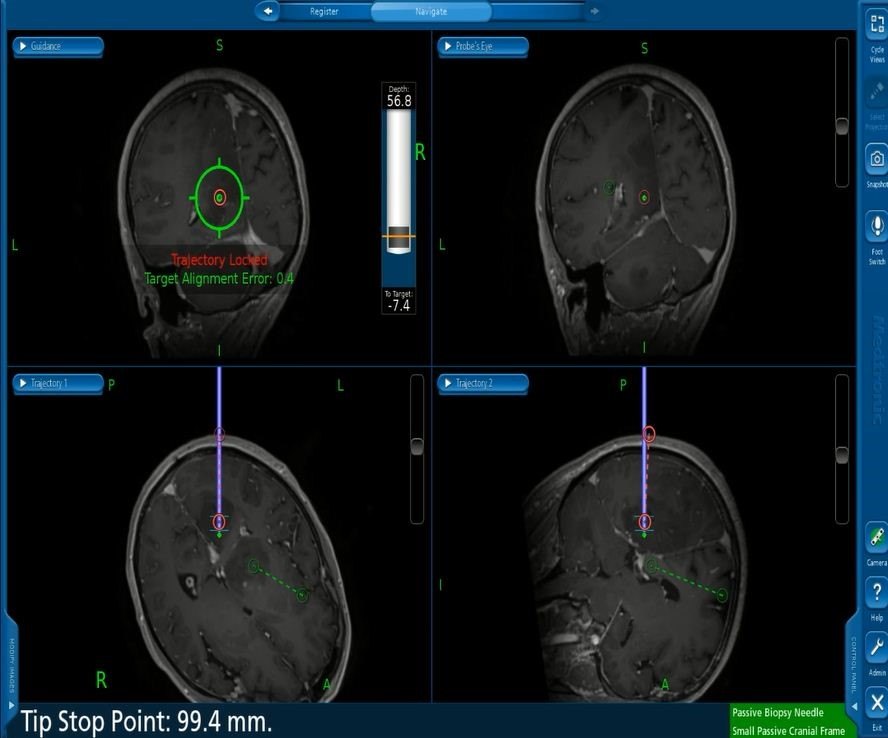

患者局麻性行神经导航下脑立体定向活检术,穿刺八点为左侧枕叶深部病变,术后病理提示:胶质增生。

患者随访数月后,复查发现病变有增大趋势,故行第二次活检术。

此次穿刺靶点为左侧丘脑和左侧诊断两个部位。

术后病理提示:左侧枕叶:弥漫性星形细胞瘤(WHO III级;IDH野生型);左侧丘脑:胶质母细胞瘤(WHO IV级;IDH野生型)。

从该病例我们吸取的经验为:该病例第一次活检为胶质细胞增生,随访数月后进展为弥漫性胶质瘤,且另外一个病灶为胶质母细胞瘤。因此对于颅内多发病灶,尽可能对多个病灶、每个病灶多个靶点进行取材,才有机会提高阳性率。